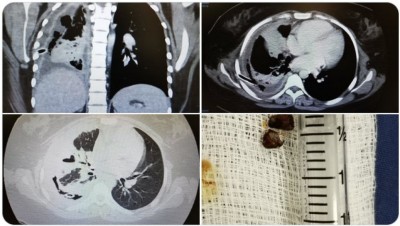

ފުއްޕާމޭގެ ބަލިތަކަށް ޚާއްސަ ޑޮކްޓަރެއް ކަމަށްވާ ޑރ. މުހައްމަދު އިސްމާއީލް ރޭ ޓްވިޓާގައި ހިއްސާ ކުރައްވާފައިވަނީ މިފަދަ ނުރައްކާތެރި ހާދިސާއެކެވެ. ފުއްޕާމޭގައި ވަރަށް ބޮޑަށް އިންފެކްޝަން އުފެދިފައި ހުރި ޒުވާން އަންހެން ކުއްޖެއްގެ ވާހަކައެވެ.

ޑރ. ވިދާޅުވިގޮތުގައި އެކުއްޖާގެ ފުއްޕާމޭގައި އިންފެކްޝަން އުފެދި ނޭވާލާ ނިޒާމުގައި ފެން އުފެދިފައި ހުރުމުން އިތުރަށް ހެދި ތަހުލީލުތަކުން ހާމަވީ ސުޕާރީ ފުކެއްގެ ސަބަބުން އެކުއްޖާގެ ފުއްޕާމޭގެ ކަނާތްފަޅި މުޅީން ބެދިފައިވާ ކަމެވެ.

ބްރޯންކޮސްކޮޕީ [ފުއްޕާމޭގައި މައްސަލައެއް ހުރިތޯ ބެލުމަށް ހޮޅި ލައްވައިގެން ހަދާ ޓެސްޓެއް] ހެދުމުން ލިބިގެންދިޔައީ ކުއްލި ހައިރާން ކަމެއް. އެކުއްޖާގެ ފުއްޕާމޭގެ ކަނާތްފަޅި ބެދިފައި ހުރީ ސުޕާރީ ފުކެއް ތާށިވެގެން.ޑރ. މުހައްމަދު އިސްމާއީލް

ޑރ. މުހައްމަދު އިސްމާއީލް ޓްވިޓާގައި ހިއްސާކުރައްވާފައިވާ ފުއްޕާމޭގެ އެކްސްރޭ

ދުފާއިރު ބައެއްފަހަރު ފޯއްކޮށި އަރާގޮތްވަނީ މިހެންވެއެވެ. ފޯކަކީ އަނގަމީރުކޮށްލަން ކާއެއްޗެއް ނަމަވެސް ދިވެހީންގެ ތެރޭގައި ބަނޑުކެއުމުގެ އުސޫލުން އެއްފަހަރާ ބައިވަރު ސުޕާރީ ކާ މީހުން މަދެއް ނޫނެވެ. އެކުއްޖާގެ މޭގައި އިންފެކްޝަން އުފެދުނު ސަބަބު ދެނެގަތުމަށް ސުވާލު ކުރުމުން ވަރަށް ގިނައިން ސުޕާރީ ކާ ކަމަށް އޭނާ އެއްބަސްވި ކަމަށް ޑރ. މުހައްމަދު އިސްމާއީލް ވިދާޅުވިއެވެ.